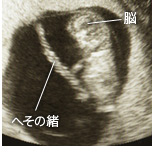

やっと脳の原型が完成。記憶の機能をつかさどる海馬もできてきます。また「気持ちいい」,「不快」などを感じる、感情のもとが生まれ始め、心ができるのももうすぐ!

毎日5千万~6千万個もの脳細胞神経が、猛スピードで増殖しています。内臓の基礎もできあがり、日々機能が発達しています。それにともなって、厚みを増した皮膚が体内部の器官を保護。皮膚の表面に産毛も生え始め、必要な機能をすべて備えた体にまで成長しています。

赤ちゃんが指しゃぶりを始めます。手や足など、体の部位を別々に動かせるようになるので、手足の指を上手に口で吸います。また、聴覚が完成するのは7ヶ月頃ですが、大きな音にはこの時点でも反応します。